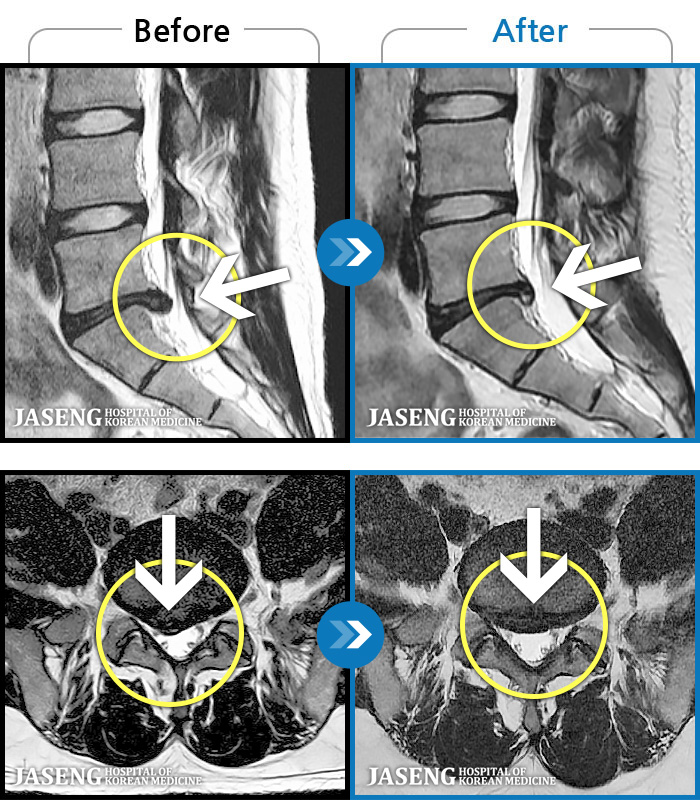

• 허리디스크